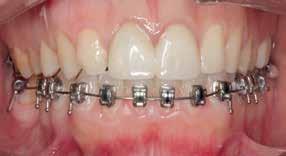

A 33 year old male presented to the orthodontic clinic referred by his prosthodontist . His main concern was the overeruption of maxillary right and left second molar due to bilateral loss of second and third mandibular molars that rendered the placement of prosthodontic implant and crown not possible. The patient had a 4 unit bridge, to replace missing maxillary right first and second premolar, with a root canal treatment and crown done on maxillary right lateral incisor and left second premolar. The patient’s main condition was to reduce the orthodontic system to a minimum with no visible appliances due to the nature of his work in sales.

Placement of temporary anchorage devices (Miniscrew) in the buccal and palatal side of the maxillary second molars in order to orthodontically intrude those teeth and create the required biological space for implant and crown placement in the mandibular posterior molar region(Figure 3).

Interproximal reduction in the area between maxillary first and second molar is necessary to allow the intrusion of the second molar without being hindered by the proximal contact of the first molar.(figure 4)

- 2 Buccal (1.6 mm diameter 8mm length) infra-zygomatic mini screw on upper 2nd molars of each side were placed this high in order not to interfere with the intrusive movement.

- 2 Palatal (1.8 mm diameter 8 mm length) placed in the midpalatal suture and another halfway the distance between the left second molar and the mid-palatal suture .

- The mini-screws were placed in a way that the resultant forces on each side are 120-150 g of force leading to close to pure intrusion of 2nd molars .

Figure 3 Figure 4

The patient presented to the clinic every 6 weeks for chain replacement because slow intrusion is needed. The 2nd molar was blocked below the distal contact area of the 1st molar, monitored IPR was carried out between the 1st and 2nd molar on both sides to facilitate the intrusive movement. The treatment took 10 months with 7 appointments.